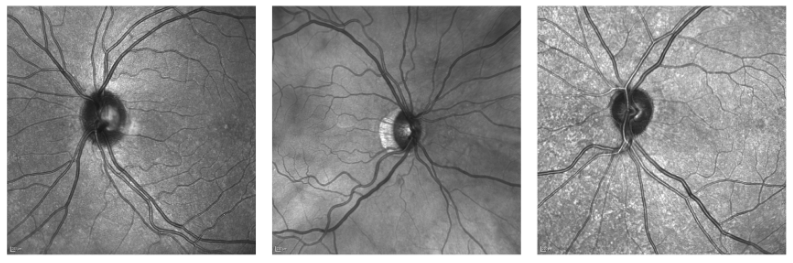

The retinal vasculature provides important clues in the diagnosis and monitoring of systemic diseases including hypertension and diabetes. The microvascular system is of primary involvement in such conditions, and the retina is the only anatomical site where the microvasculature can be directly observed. The objective assessment of retinal vessels has long been considered a surrogate biomarker for systemic vascular diseases, and with recent advancements in retinal imaging and computer vision technologies, this topic has become the subject of renewed attention. In this paper, we present a novel dataset, dubbed RAVIR, for the semantic segmentation of Retinal Arteries and Veins in Infrared Reflectance (IR) imaging. It enables the creation of deep learning-based models that distinguish extracted vessel type without extensive post-processing.